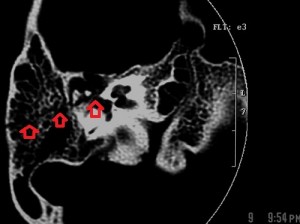

Images A and B are bone-window axial sections of the petrous portions of the right and left temporal bones taken at slightly different levels. Both show longitudinal fractures of the petrous pyramids with slightly different orientations (see the arrows). In addition, there is a fracture line through the anterior right basi-occiput, arrowed on image B.

On the right, the fracture line extends into the right middle ear, across the tegmen tympani and into the middle cranial fossa while on the left it stops at the external auditory meatus. The right ossicular chain is dislocated (incudostapedial joint) but the left chain and the right and left otic capsules are preserved. There is effluent in the right mesotympanum, the reason for a right ottorhea at presentation. There is no fluid in the left middle and external ear. Although the images are not included, there are no injuries to the internal auditory canals

2. Fracture of the anterior basi-occiput.